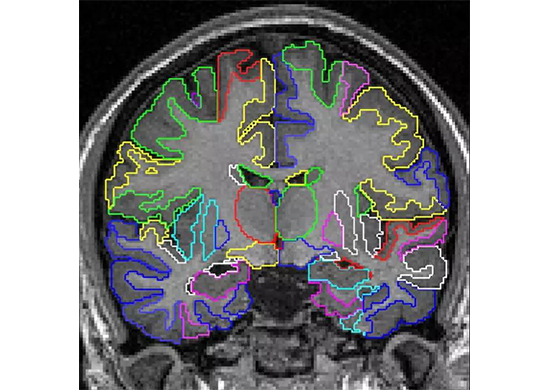

图像处理之医学图像

医学图像处理是目前人工智能在医疗领域的典型应用,它的处理对象是由各种不同成像机理,如在临床医学中广泛使用的核磁共振成像、超声成像等生成的医学影像。

传统的医学影像诊断,主要通过观察二维切片图去发现病变体,这往往需要依靠医生的经验来判断。而利用计算机图像处理技术,可以对医学影像进行图像分割、特征提取、定量分析和对比分析等工作,进而完成病灶识别与标注,针对肿瘤放疗环节的影像的靶区自动勾画,以及手术环节的三维影像重建。

该应用可以辅助医生对病变体及其他目标区域进行定性甚至定量分析,从而大大提高医疗诊断的准确性和可靠性。另外,医学图像处理在医疗教学、手术规划、手术仿真、各类医学研究、医学二维影像重建中也起到重要的辅助作用。